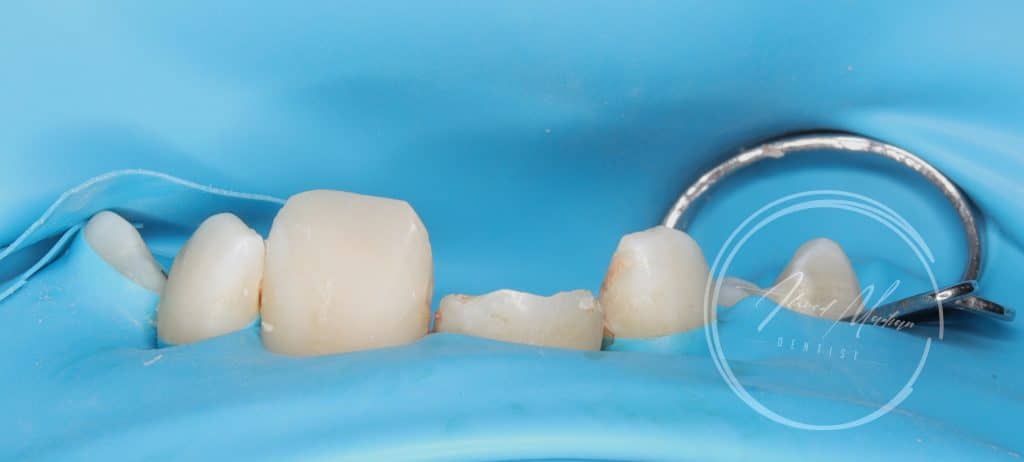

11 – gingivectomy , DME , build up , cleaning and shaping , intra canal medication and patient will be under follow up for the next month considering the initiation of internal or external resorption , after follow up RCT , fiber post will be placed

12 – direct composite restoration

Now patient situation is stabilized and will under go regular follow ups and will be referred to orthodontist for further assessment